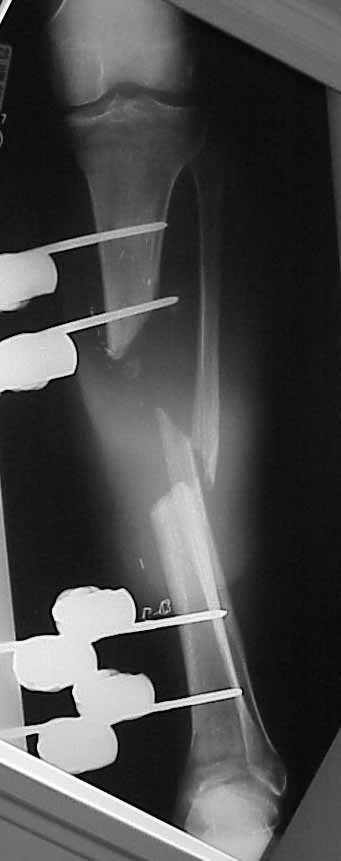

45 year old healthy non-smoker is six weeks post type 3B open tibial fracture. Latissimus flap looks perfect. Tibia is about 20 degrees externally rotated and in valgus. Intact pulses and sensation. Defect is 10-11 cm.

I'd love to nail and graft this one, rather than starting a 9 month Ilizarov lengthening.

Is it too big to nail and graft?

Does this require a bifocal lengthening?